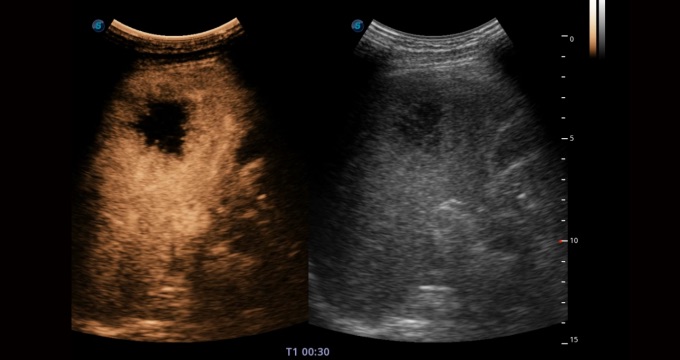

腹部应用

造影成像功能和定量分析工具包使医生能够准确的评估血流灌注情况。独特的动态声压控技术有效控制造影剂的声压,保证造影剂持续时间,方便医生观察病变灌注的延迟相位。